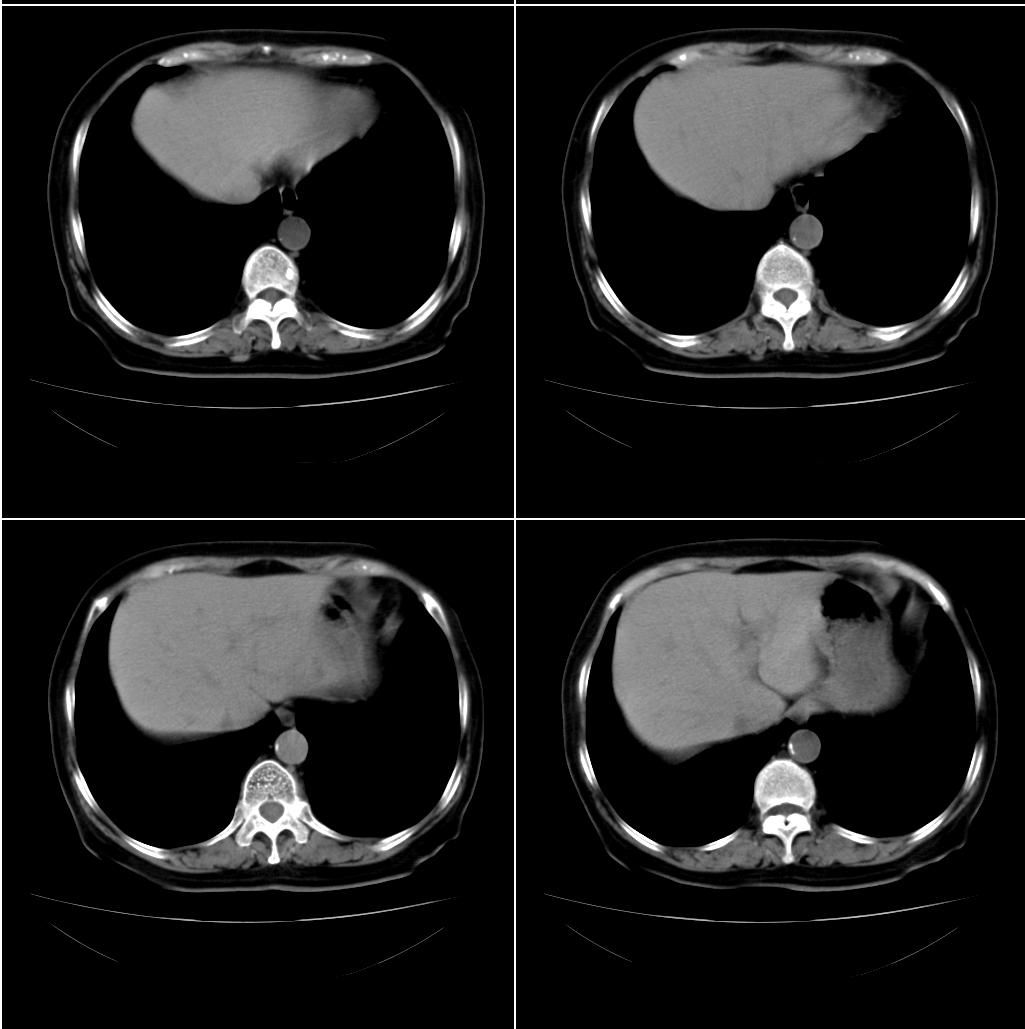

以下是引用sxlcbc在2007-12-23 4:27:00的发言:[br]气管源性肿瘤觉得有点不靠谱啊,看上去气管是受压改变的。更像是上段食管的改变,周围淋巴结肿大,食管受压。看看以下六幅图片:[br]不过,有一点不好理解:食管肿瘤应该有食道症状的,再说食管癌出现周围这么大的淋巴结也不多见啊,如果考虑淋巴瘤倒是更合理一点,这样气管,食管受压改变也许更合理一些。[br][br]